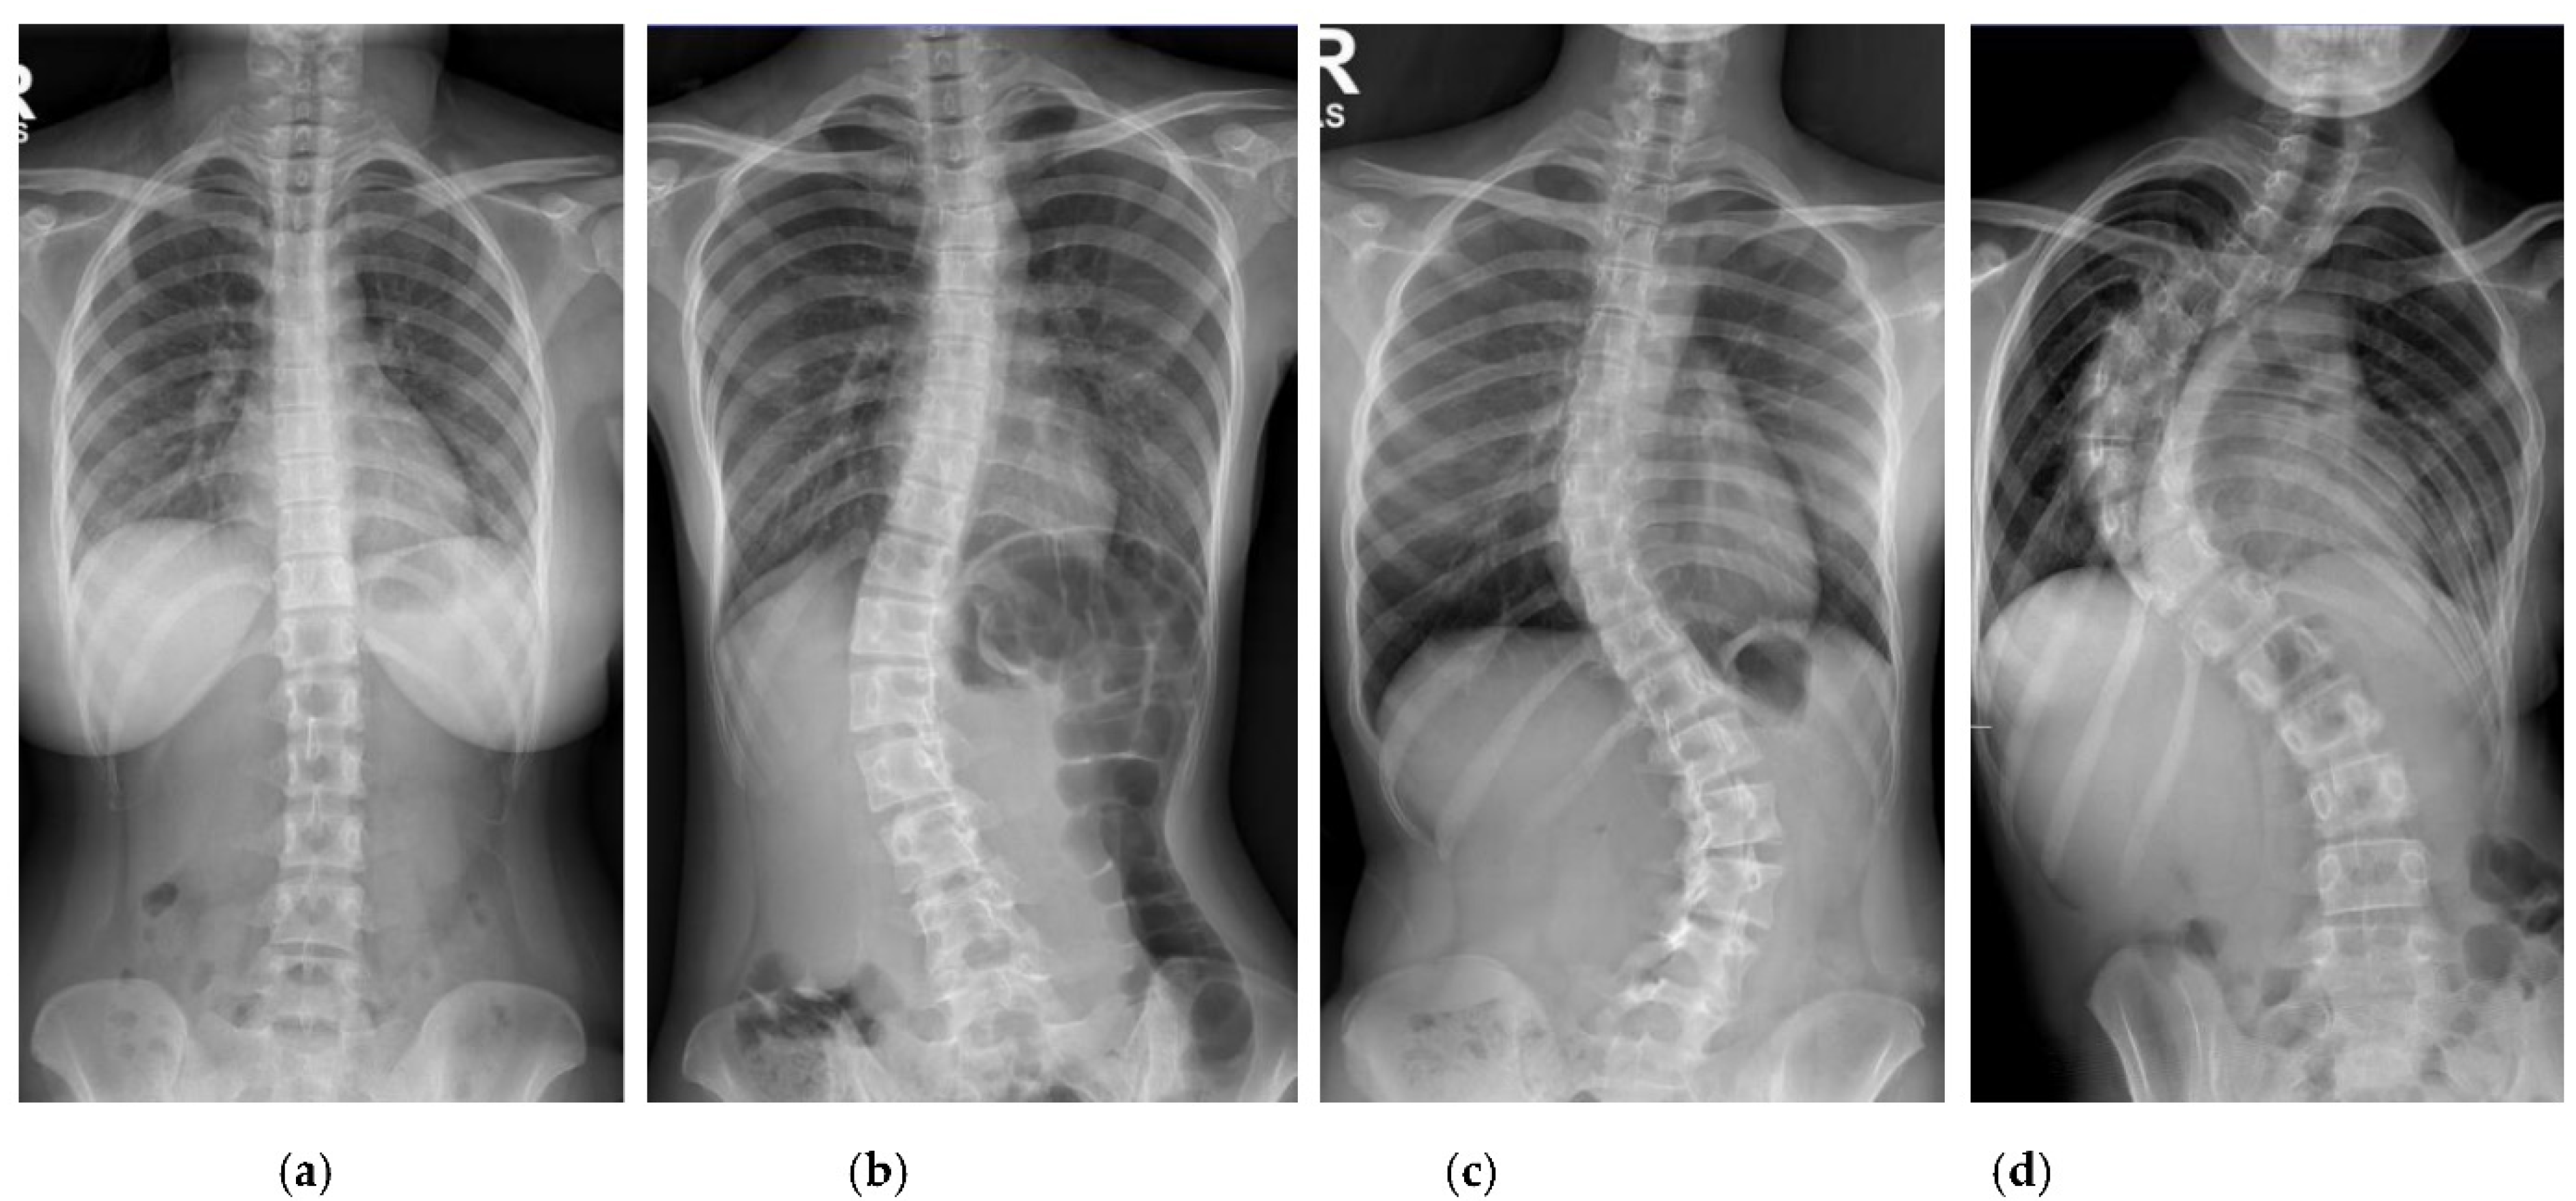

The collection and labeling of spinal images were performed by the public AASCE MICCAI 2019 anterior-posterior X-ray images dataset [18]. The input images vary in size from 359 × 973 to 1427 × 3755. Some challenging images can be handled due to our large number of training image conditions, which include images with different noise, contrast, lighting conditions, and spines with high CA, as shown in Figure 1. Each image contains 17 vertebrae from the thoracic (upper spine) and lumbar (lower spine) regions. The image input resolution is set to 1024 × 512 for the algorithm development. Each vertebra is located by four corner landmarks. The ground-truth of the 68 landmarks or points in each image is provided by the dataset.

Figure 1.

Examples of some challenging image conditions: (a) Image with noise; (b) high contrast image; (c) low light image; (d) spine with high CA.